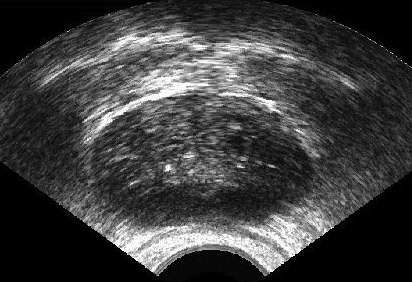

We generated 500 images from their corresponding gold-standard images. Furthermore, we generated 20 different segments for each image, assuming that there were 20 users. Figure 4 shows three examples of real and synthetic TRUS images. One should bear in mind that the purpose here was not to simulate the images realistically, but rather to have a base from which to generate variable segments from a perfect segment. Figure 5 shows an example of the gold segments and simulated user contours. The variability, coupled with the gold segment, is what is needed to validate our approach.

Sample images are depicted in Figure 6 (top row). Generally, one assumes that prostate segmentation is a relatively easy task. However, the variability of such segmentation remains considerable, and this is conspicuous in Figure 6 (bottom row).